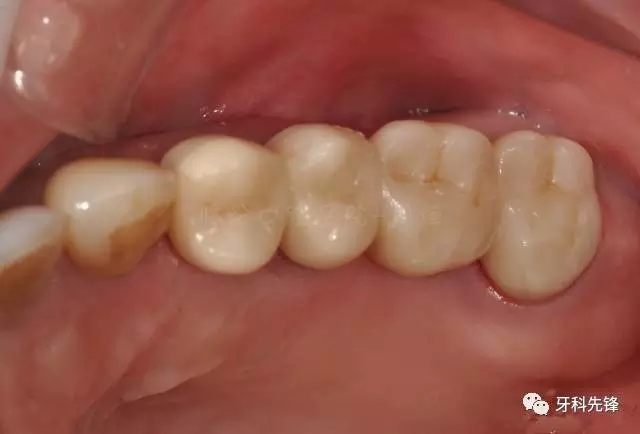

圖2  術(shù)前側(cè)位咬頜照

檢查:15 16 17 烤瓷冠修復(fù)體,崩瓷,邊緣不密合,食物嵌塞,齦下牙石II°,冷熱診無不適,叩診(+),牙齦輕微紅腫。